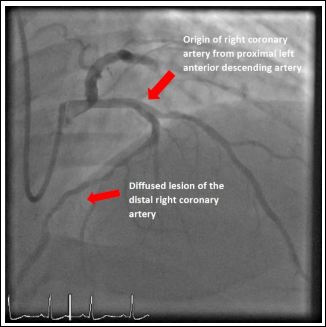

The third case was a 51-year-old male with no prior history of ischaemic heart disease presenting with unstable angina. His admission ECGs was unremarkable. Diagnostic coronary angiogram was done and it showed a right coronary artery arising from the proximal LAD. Mid LAD had severe diffuse stenosis distal to the origin of RCA. There was a 70% stenosis in the proximal RCA and a further 80% stenosis in the distal RCA (Figure 5). PCI to mid LAD and proximal RCA was done (Figure 6). It was an uncomplicated procedure and patient was discharged after 4 days of hospital stay. The echocardiography did not reveal any associated structural heart disease.

Figure 5: Anomalous origin of right coronary artery from the proximal left anterior descending artery and diffused lesion of the distal right coronary artery.

Figure 6: Anomalous origin of right coronary artery from the proximal left anterior descending artery (post PCI).